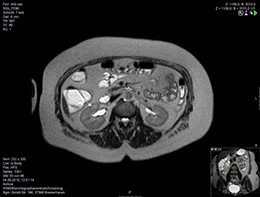

Bei der Sellink-CT und der Sellink-MRT handelt es sich um kontrastmittelunterstützte Schnittbilduntersuchungen des Dünndarmes, welche die frühere Röntgen-Doppelkontrast-Untersuchung abgelöst haben. Die Untersuchungen sind bei bestimmten entzündlichen, seltener auch tumorösen Erkrankungen des Dünndarmes angezeigt. Beide Untersuchungen verlaufen im wesentlichen wie eine normale Abdomen-CT bzw. Abdomen-MRT, die notwendigen Laborbestimmungen sind daher dieselben. Wie für diese ist auch die intravenöse Injektion eines Kontrastmittels erforderlich (siehe auch den Abschnitt Computertomographie bzw. Magnetresonanztomographie).

Für die Sellink-Untersuchung ist allerdings darüber hinaus auch eine Darmvorbereitung mit flüssiger Ernährung und Nahrungskarenz erforderlich, deren Details Ihnen vor der Untersuchung mitgeteilt werden.

Vor der CT-Untersuchung wird unter Röntgenkontrolle eine schmale Sonde von der Nase bis in den Dünndarm (naso-duodenale Sonde) geführt, über die 2l Methylzelluloselösung in den Dünndarm geleitet werden, um diesen für die Untersuchung optimal zu erweitern.

Vor der MRT-Untersuchung muß der Patient 2l Mannitol-Lösung selbst trinken, um den Darm zu entfalten.

Dann erfolgt in beiden Untersuchungen eine intravenöse Injektion von Butylscopolamin (Buscopan®), um den Darm zu entspannen, was die Sehfähigkeit und die Fahrtüchtigkeit einschränken kann. Bitte planen Sie dies und eventuell eine Begleitung für den Nachhauseweg ein. Die anschließende CT- bzw. MRT-Untersuchung wird unter intravenöser Kontrastmittelgabe nach einem festgelegten Protokoll in Rückenlage des Patienten durchgeführt. Die Befundung der erstellten Aufnahmen erfolgt an Hochleistungsrechnern durch unsere Radiologen mit Hilfe spezieller Programme nicht nur im Hinblick auf den Dünndarm, sondern für das gesamte Abdomen.